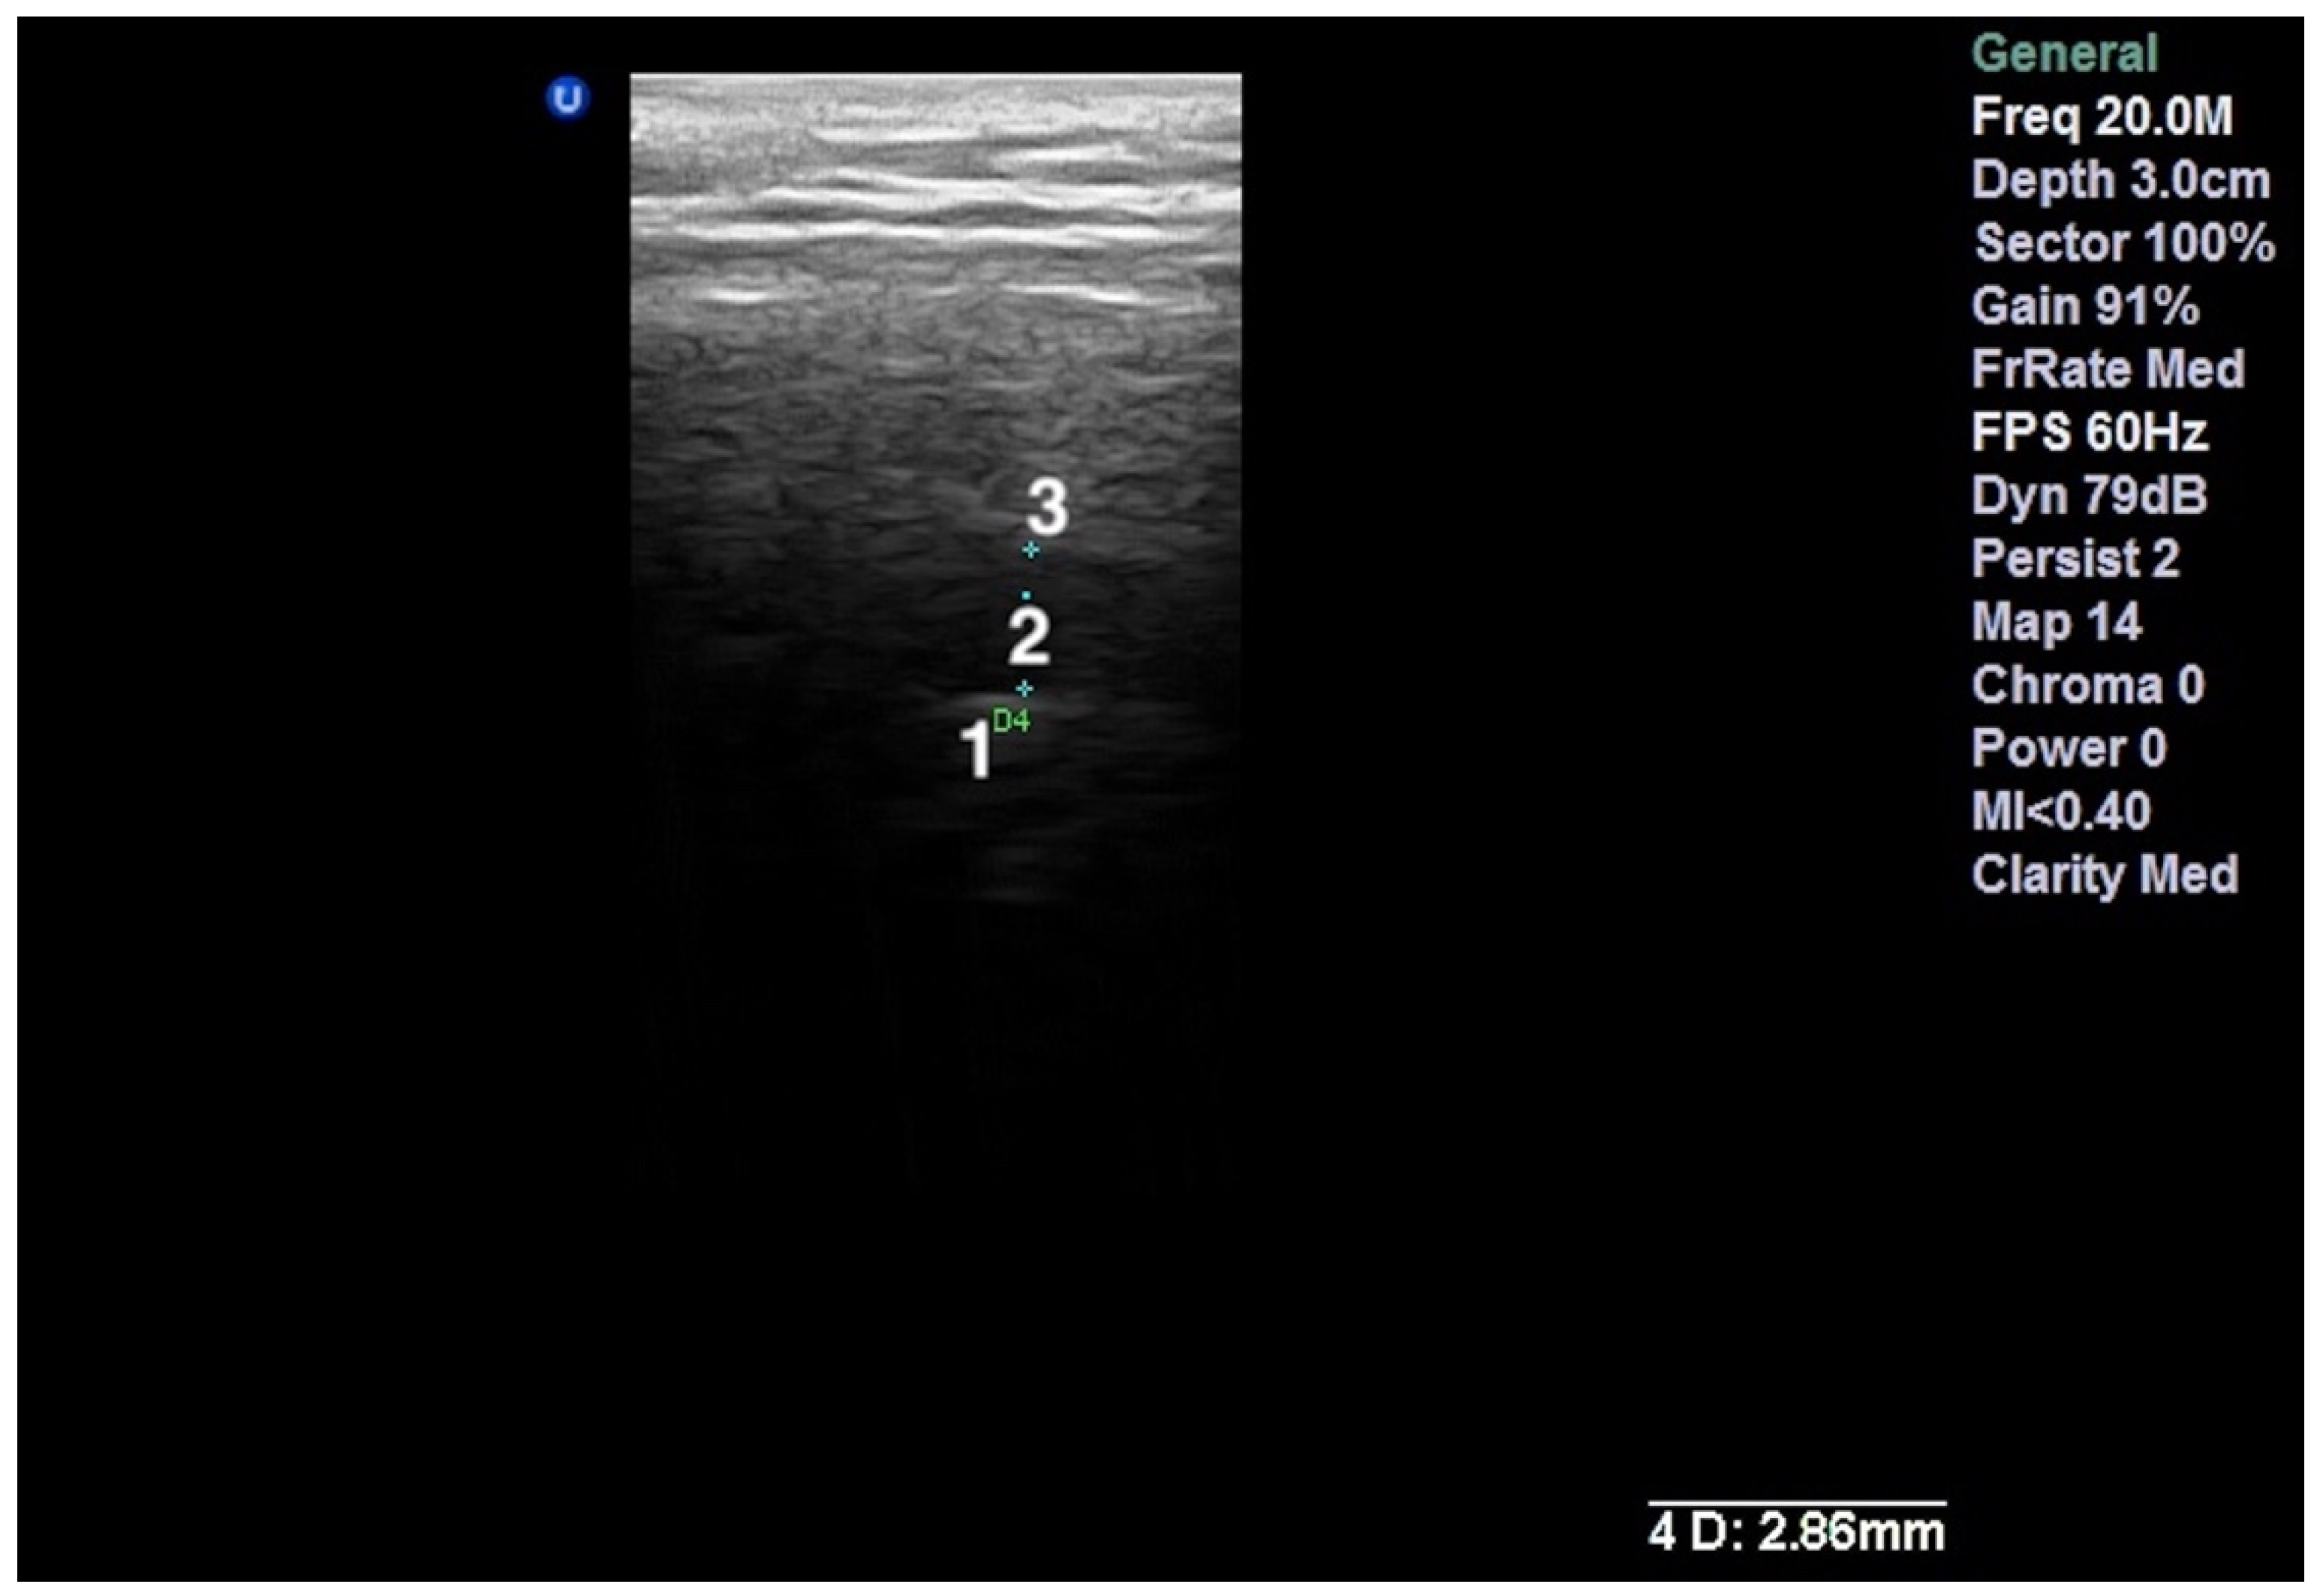

2.3. The Ultrasound Examination

- Talmaceanu, D.; Lenghel, L.M.; Bolog, N.; Stanila, R.P.; Buduru, S.; Leucuta, D.C.; Rotar, H.; Baciut, M.; Baciut, G. High-resolution ultrasonography in assessing temporomandibular joint disc position. Med. Ultrason. 2018, 20, 64–70. [Google Scholar] [CrossRef] [Green Version]

- Talmaceanu, D.; Lenghel, L.M.; Bolog, N.; Buduru, S.; Leucuta, D.; Horatiu, R. High-resolution ultrasound imaging compared to magnetic resonance imaging for temporomandibular joint disorders: An in vivo study. Eur. J. Radiol. 2020, 132, 109921. [Google Scholar] [CrossRef]

- Manfredini, D.; Tognini, F.; Melchiorre, D.; Zampa, V.; Bosco, M. Ultrasound assessment of increased capsular width as a predictor of temporomandibular joint effusion. Dentomaxillofac. Radiol. 2003, 32, 359–364. [Google Scholar] [CrossRef]

- Bas, B.; Yılmaz, N.; Gökce, E.; Akan, H. Ultrasound assessment of increased capsular width in temporomandibular joint internal derangements: Relationship with joint pain and magnetic resonance grading of joint effusion. Oral Surg. Oral Med. Oral Pathol. Oral Radiol. Endod. 2011, 112, 112–117. [Google Scholar] [CrossRef] [PubMed]